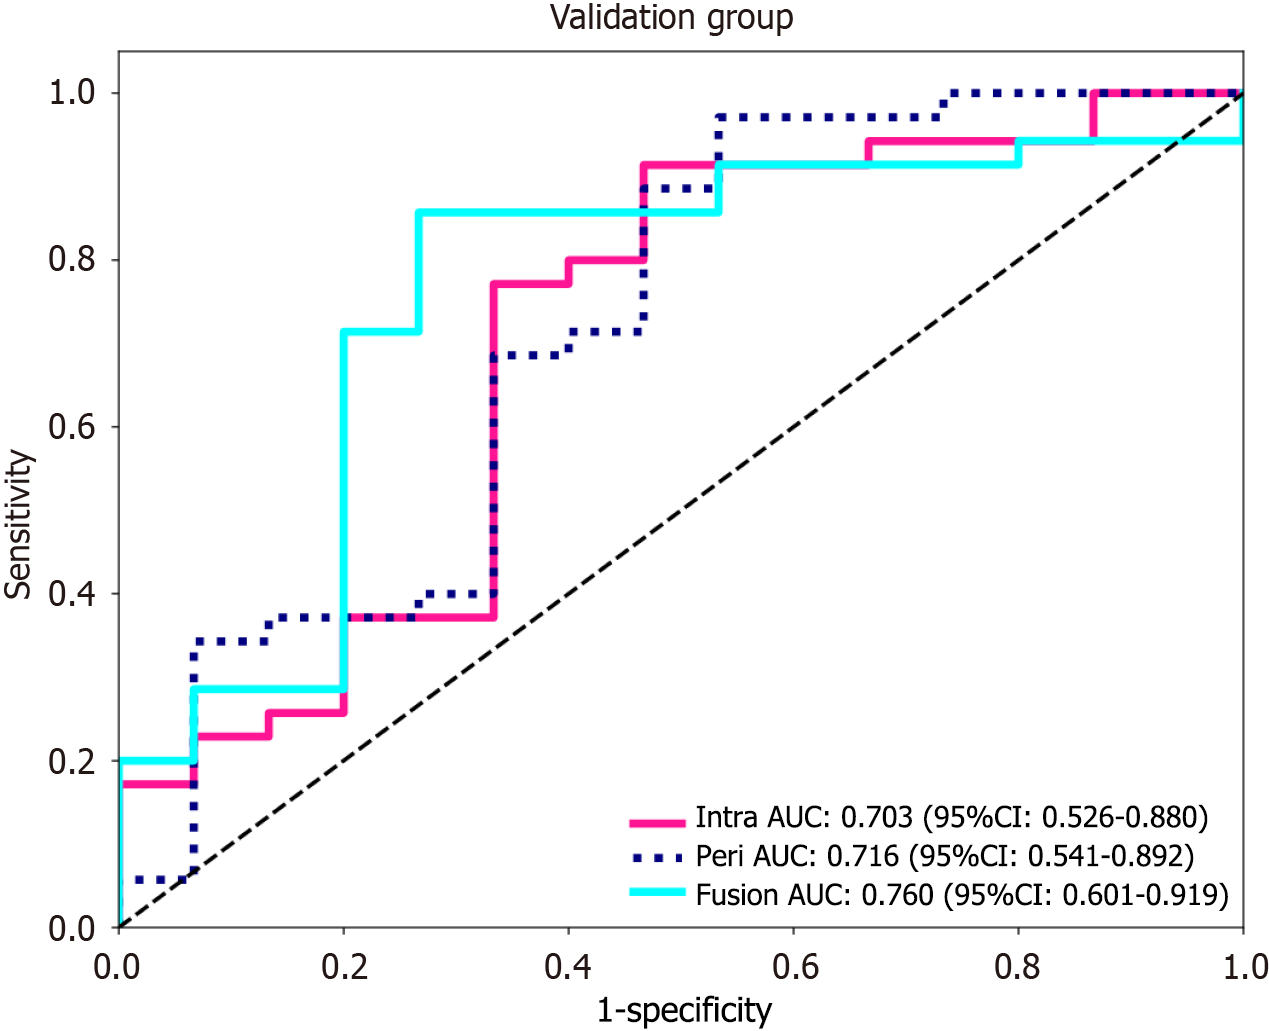

Using the logistic regression algorithm, we constructed predictive models and selected the best-performing model. Among the three models in the validation group, the fusion model had the highest predictive capability, with an AUC of 0.760 (0.601-0.919), which surpassed those of the intratumoral model [AUC of 0.703 (0.526-0.880)] and the peritumoral model [AUC of 0.716 (0.541-0.892)], as shown in Figure 4. The ROC curve for the training group is presented in Supplementary Figure 4. To further demonstrate the performance of the model, we plotted waterfall plots for each of the three prediction models. The results showed that the three models have high accuracy in assessing the expression level of Ki-67. The waterfall plot of the validation group is shown in Figure 5, and the waterfall plot of the training group is shown in Supplementary Figure 5.